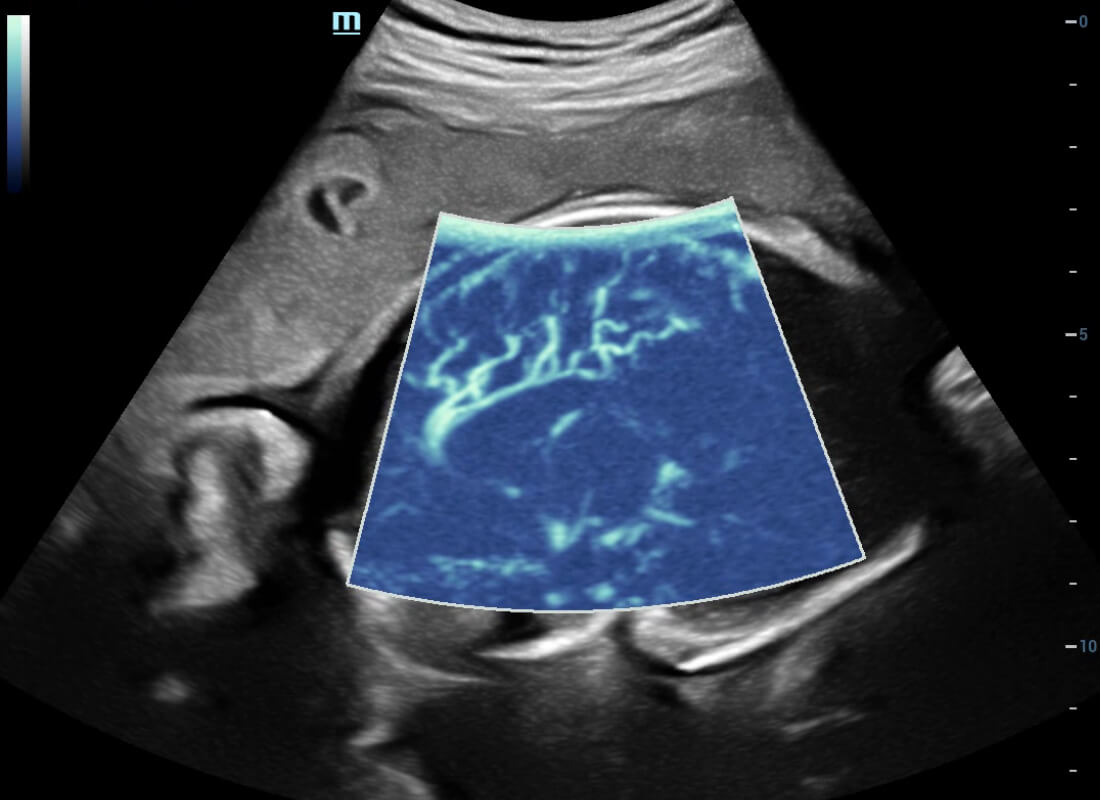

Central nervous system (CNS) malformations are one of the most common congenital abnormalities. Unfortunately, due to imaging limitations such as poor fetal position, acoustic shadowing, and operatorsŌĆÖ poor scanning skills, the MSP is particularly difficult to find in a 2D ultrasound. In this case, a faster and more user-friendly method, which automatically displays the standard planes together with the required measurements in a fetal CNS examination, could significantly boost both the quality and efficiency of clinical diagnoses.?NuewaŌĆÖs intelligent solution of fetal brain can realize automatic acquisition of brain volume data based on intelligent recognition of CNS application scenarios, intelligent generation of four fetal brain standard planes including MSP, automatic measurement of CNS biological items and automatic evaluation of fetal brain volume. More importantly, Nuewa's leading color Doppler technology can provide a clear and sensitive dynamic display of blood flow in the tiny vessels.